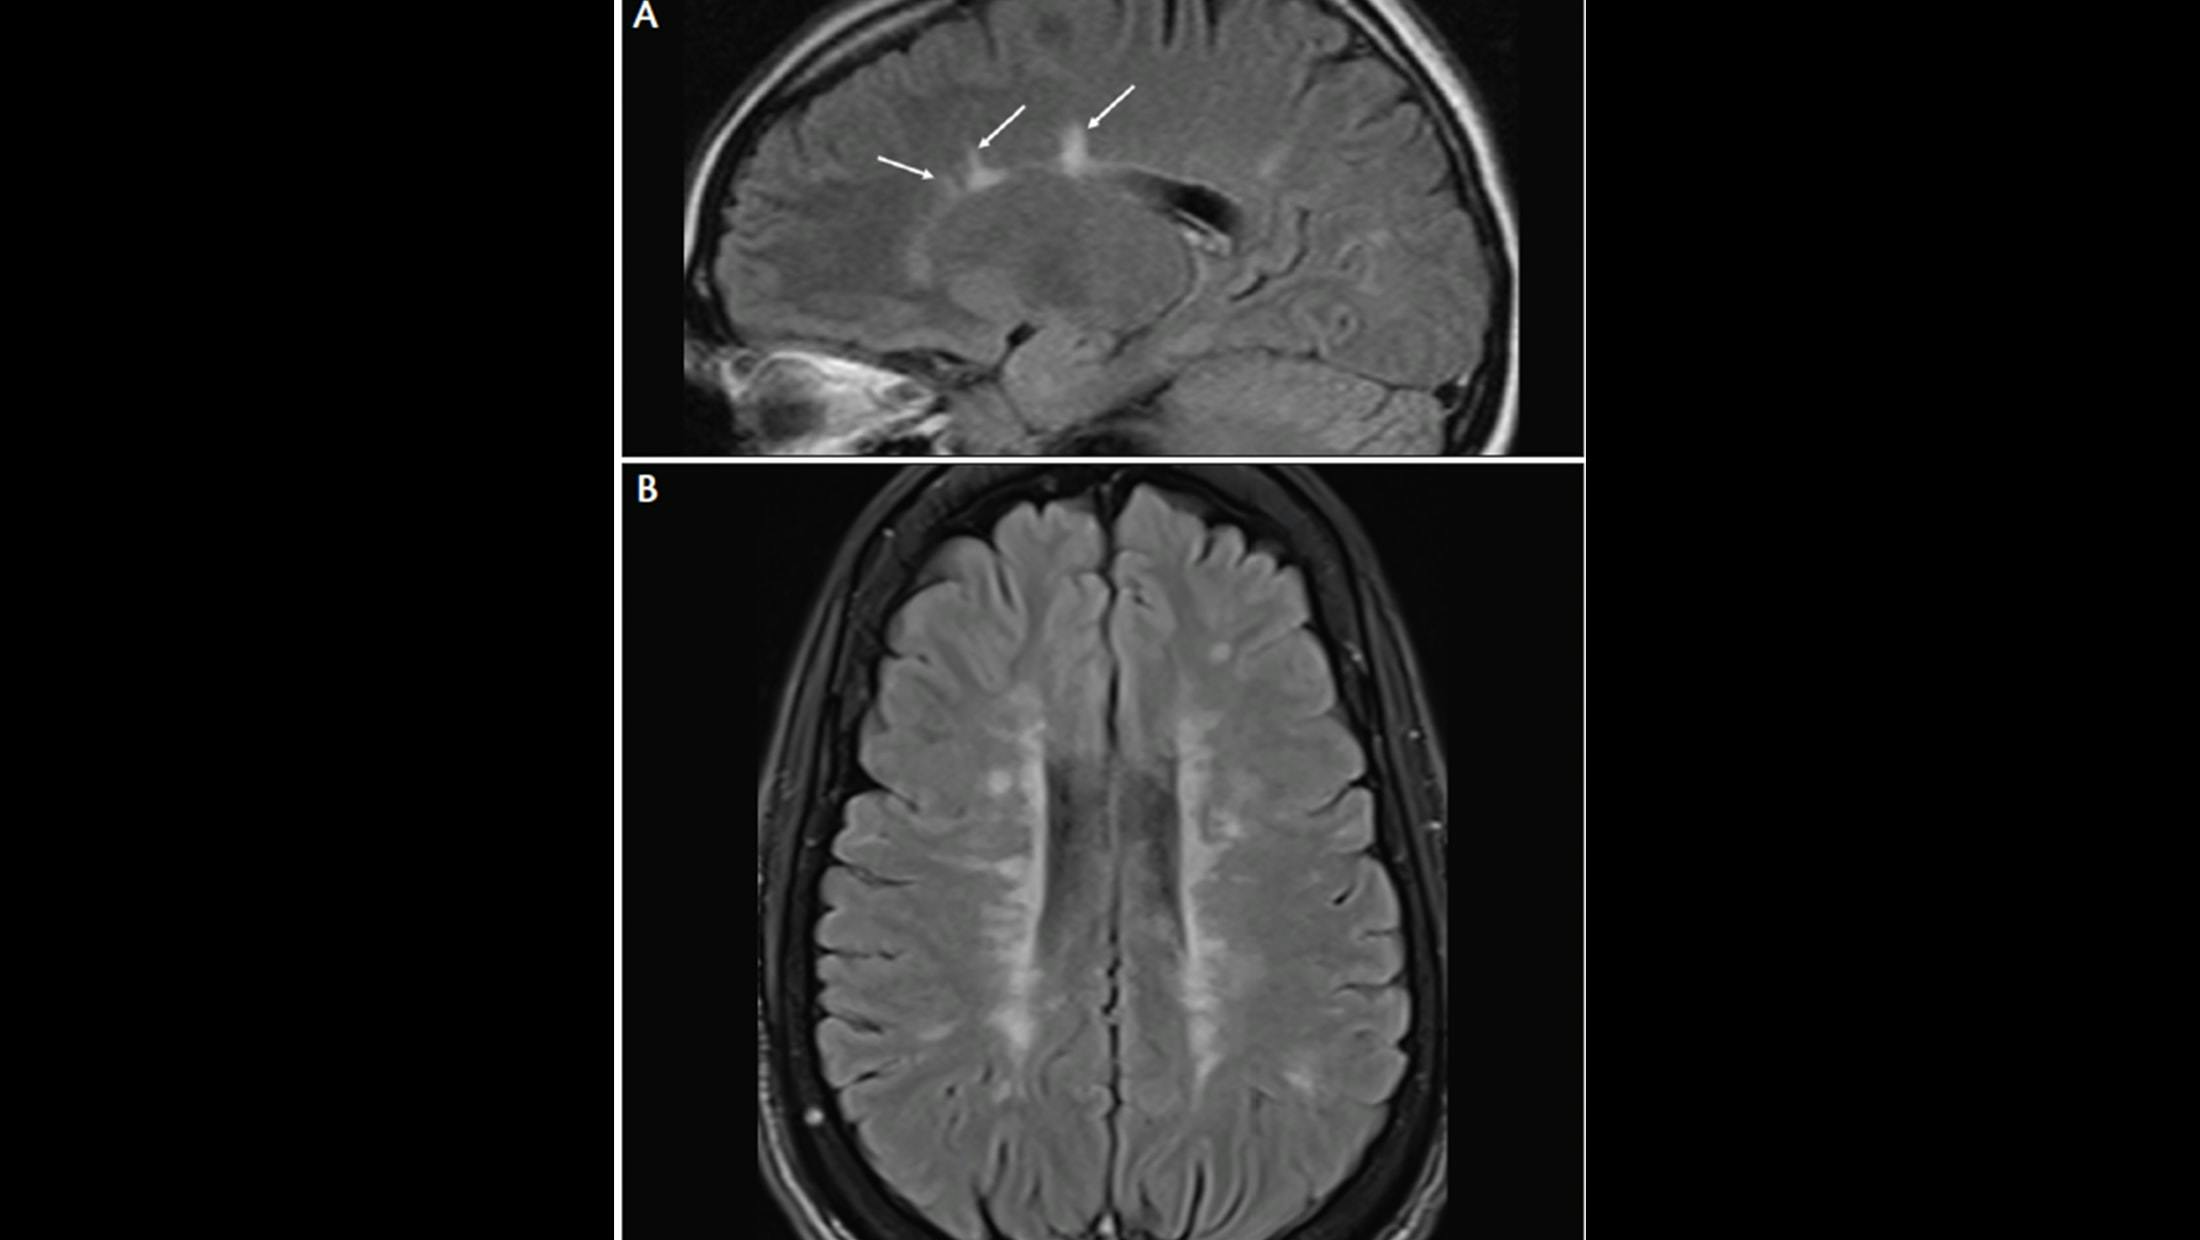

A. Lesions adjacent to lateral ventricle (Dawson’s fingers). MRI from a patient with early MS shows a few Dawson’s fingers on sagittal fluid-attenuated inversion recovery (FLAIR) image.

B. Lesions adjacent to lateral ventricle (Dawson’s fingers). MRI from a patient with more advanced MS shows numerous Dawson’s fingers on axial FLAIR image.